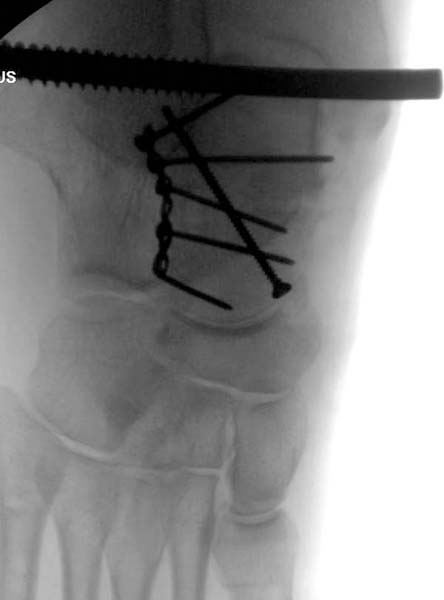

> После спадения отека на стопе произведена фиксация тарана. Кстати, коллеги

> пересмотрели первоначальную консультацию по позвоночнику и на двух уровнях

> провели фиксацию. Из-за длительного постельного режима без нагрузки таз не

> стали оперировать...